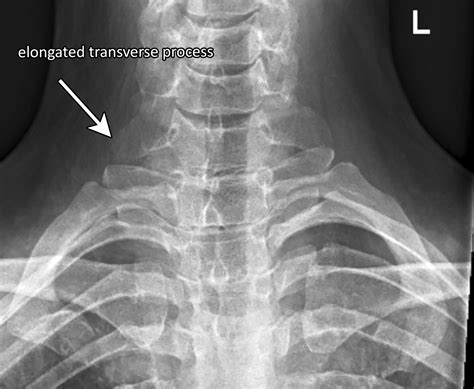

Thoracic outlet syndrome can be categorized into three main types based on what is being compressed:

• Neurogenic TOS: Compression of the brachial plexus, a network of nerves that control muscles and sensation in the shoulder, arm, and hand.

• Venous TOS: Compression of the subclavian vein, which can lead to blood clots.

• Arterial TOS: Compression of the subclavian artery, which can cause arm pain, numbness, and even tissue damage.